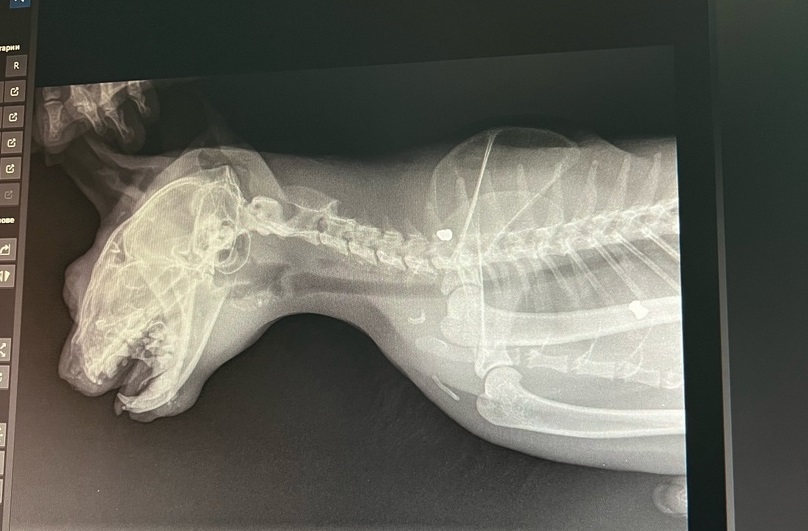

Волонтеры благотворительного фонда «Рекс» подадут заявление в полицию после гибели кота из Медвежьегорска, который вернулся домой с многочисленными переломами и пулевыми ранениями. Животному провели экстренную операцию, однако его сердце остановилось.

«Он всегда был на самовыгуле. На этот раз вернулся домой в таком состоянии, что хозяева приняли решение от него отказаться… Очевидно, что кот попал в руки к живодёрам», — написали в сообществе фонда в социальных сетях.